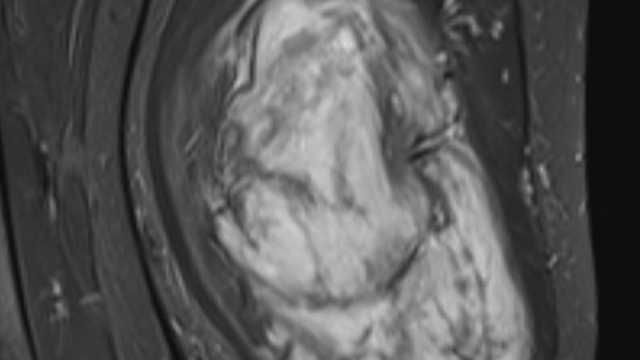

Mardin’de yaşayan H.T. (42), 3 yıl önce sağ baldırının arka kısmında oluşan ve başlangıçta yumurta büyüklüğünde olan kitlenin zamanla büyümesi üzerine Dicle Üniversitesi Tıp Fakültesi Hastanesi Ortopedi ve Travmatoloji Bölümü’ne başvurdu. Muayenede yumuşak doku kitlesi olduğu değerlendirilen şişliğin alınması için Ortopedi ve Travmatoloji Anabilim Dalı Öğretim Üyesi Prof. Dr. Emin Özkul ve ekibi tarafından ameliyat kararı verildi. Yaklaşık 2 saat süren operasyonla kitlenin çıkarıldığı, kitlenin 5 kilo 668 gram geldiği belirtildi.

Prof. Dr. Emin Özkul, vücutta görülen kitlelere büyümeden müdahale edilmesi gerektiğini ifade ederek, “Hastamız 42 yaşında bir kadın. Komşu şehir Mardin’den geldi. Bölge hastanesi olduğumuz için bu tür hastalar Mardin’den, Şırnak’tan ve diğer illerden çok geliyor. Bu hastalara önerimiz; ‘küçük bir kitle, ağrısız bir kitlem var, ele gelen bir şişliğim var ama bunda ağrı olmadığı için herhangi bir şey olmaz’ dememeli. En yakın sağlık kuruluşuna başvurup en azından kitlenin bir öneminin olup olmadığını teyit edilmesi, bir uzman tarafından bunun doğrulanmasını istiyoruz. Bu hasta da 3 yıl önce fark edilmiş küçük bir kitle, zamanla çok büyük boyutlara, yaklaşık 6 kiloya varan boyutlara varmıştı. Neredeyse bütün bacak boyu yayılan bir kitlesi mevcuttu. Bu kadar büyümenin şöyle sıkıntıları oluyor, kişinin bacağında, kolunda fonksiyon kaybına, yeri geliyor ekstremite kaybına, yani bacağını kaybetmesine yol açabilecek sıkıntılara yol açıyor. Küçükken bunlarla baş etmek daha kolay. Kişinin ekstremitesinde, bacağında, kolunda bir sıkıntı yaratmadan bunları telafi etmek, bunları alıp çıkartmak, ameliyatla bunları tedavi etmek daha kolayken bu boyutlara vardığında kişinin bacağında, kolunda fonksiyon kaybı, sakatlık riski çok yüksek oluyor. Bu sebeple küçükken önleminin alınmasında yarar var” dedi.

Kitlelerin görülmesi halinde sağlık kuruluşlarına başvurulması gerektiğini belirten Prof. Dr. Özkul, “Hastamızda yaklaşık olarak 3 yıl önce şikayetleri başlamış. Sonra zaman içerisinde hızla büyüyen bir kitleye sahipti. Şanslıydı ki herhangi bir sinirine zarar vermemişti. Hayatına fonksiyon bozukluğu olmadan devam edebilecek. Bölgemize yaşayan ve ülkemizde yaşayan herkese şunu söylüyoruz. Küçük de olsa yumuşak doku kitlelerini önemsemeleri ve uzman görüşü almalarını öneriyorum. Bu hastadan 5 kilo 668 gramlık bir kitle çıkarttık. Bu benim mesleki yaşamım boyunca çıkarttığım en büyük kitlelerden bir tanesiydi. Biraz daha büyük boyutlara varmış olsa kişinin bacağını kurtarma şansınız olmuyor. Bu sebeple bunlara dikkat etmek gerekiyor. Hızlı büyüyen bir kitleniz var ise, ağrısız da olsa mutlaka ve mutlaka tedavi için en yakın sağlık kuruluşuna veya bizim üniversitemizin polikliniklerine başvurabilirsiniz” diye konuştu.